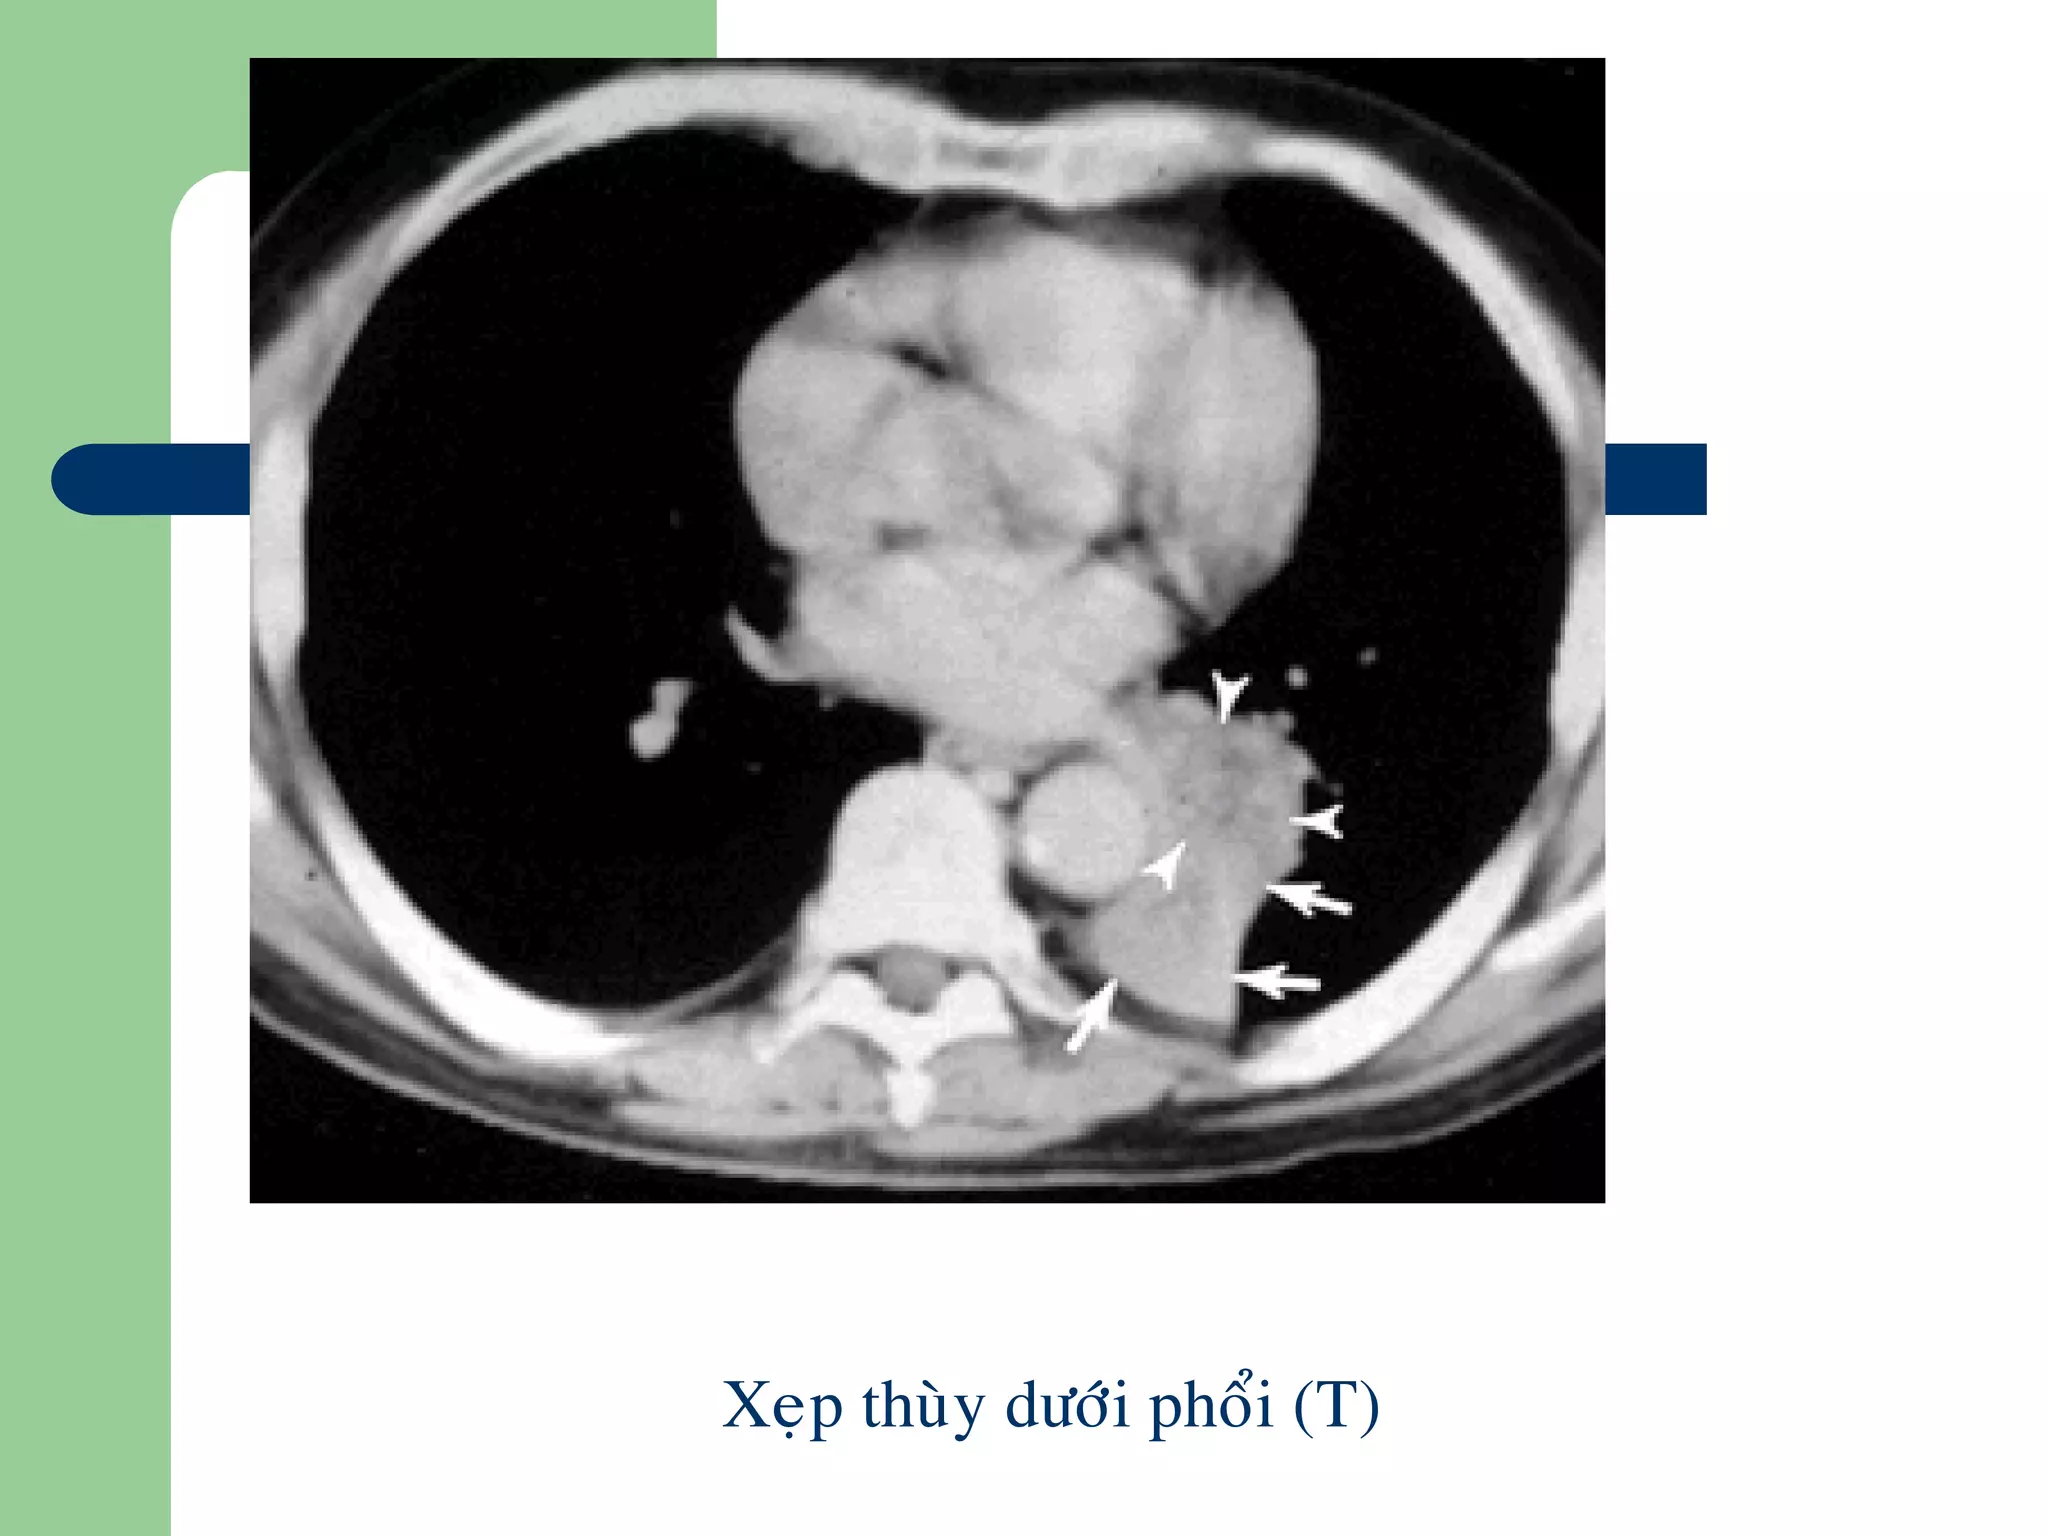

Xẹp phổi

 NN: U, viêm, nút nhầy, vật lạ

 CT: Đậm độ mô mềm, tăng quang

mạnh

Kéo các nhánh mạch máu vùng

phổi xẹp lại gần nhau

Kéo rãnh màng phổi, trung thất,

rốn phổi về phía xẹp

Nâng cao vòm hoành, hẹp khoảng

liên sườn bên phổi xep

Tăng thông khí bù trừ

Xeïp thuøy döôùi phoåi (T)